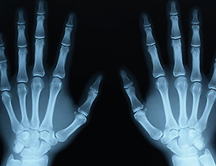

9 innovadoras aplicaciones de los rayos X

En noviembre de 1895, el físico alemán Röntgen descubrió un "rayo misterioso" que tenía el poder de producir una imagen después de atravesar carne, ropa, madera o metal, y al que bautizó con la incógnita "X". Desde entonces las aplicaciones de los rayos X se han multiplicado.

rayosxEn noviembre de 1895, el físico alemán Wilhelm Conrad Röntgen descubrió un "rayo misterioso" que tenía el poder de producir una imagen después de atravesar carne, ropa, madera o metal, y al que bautizó con la incógnita "X". Desde entonces las aplicaciones de los rayos X se han multiplicado. Además de crecer su interés para el diagnóstico médico, esta tecnología se emplea para controlar de seguridad en los aeropuertos, estudiar la calidad del jamón de bellota o encontrar la "materia perdida del universo". E incluso hay quien ha encontrado el modo de usar rayos X con fines artísticos.